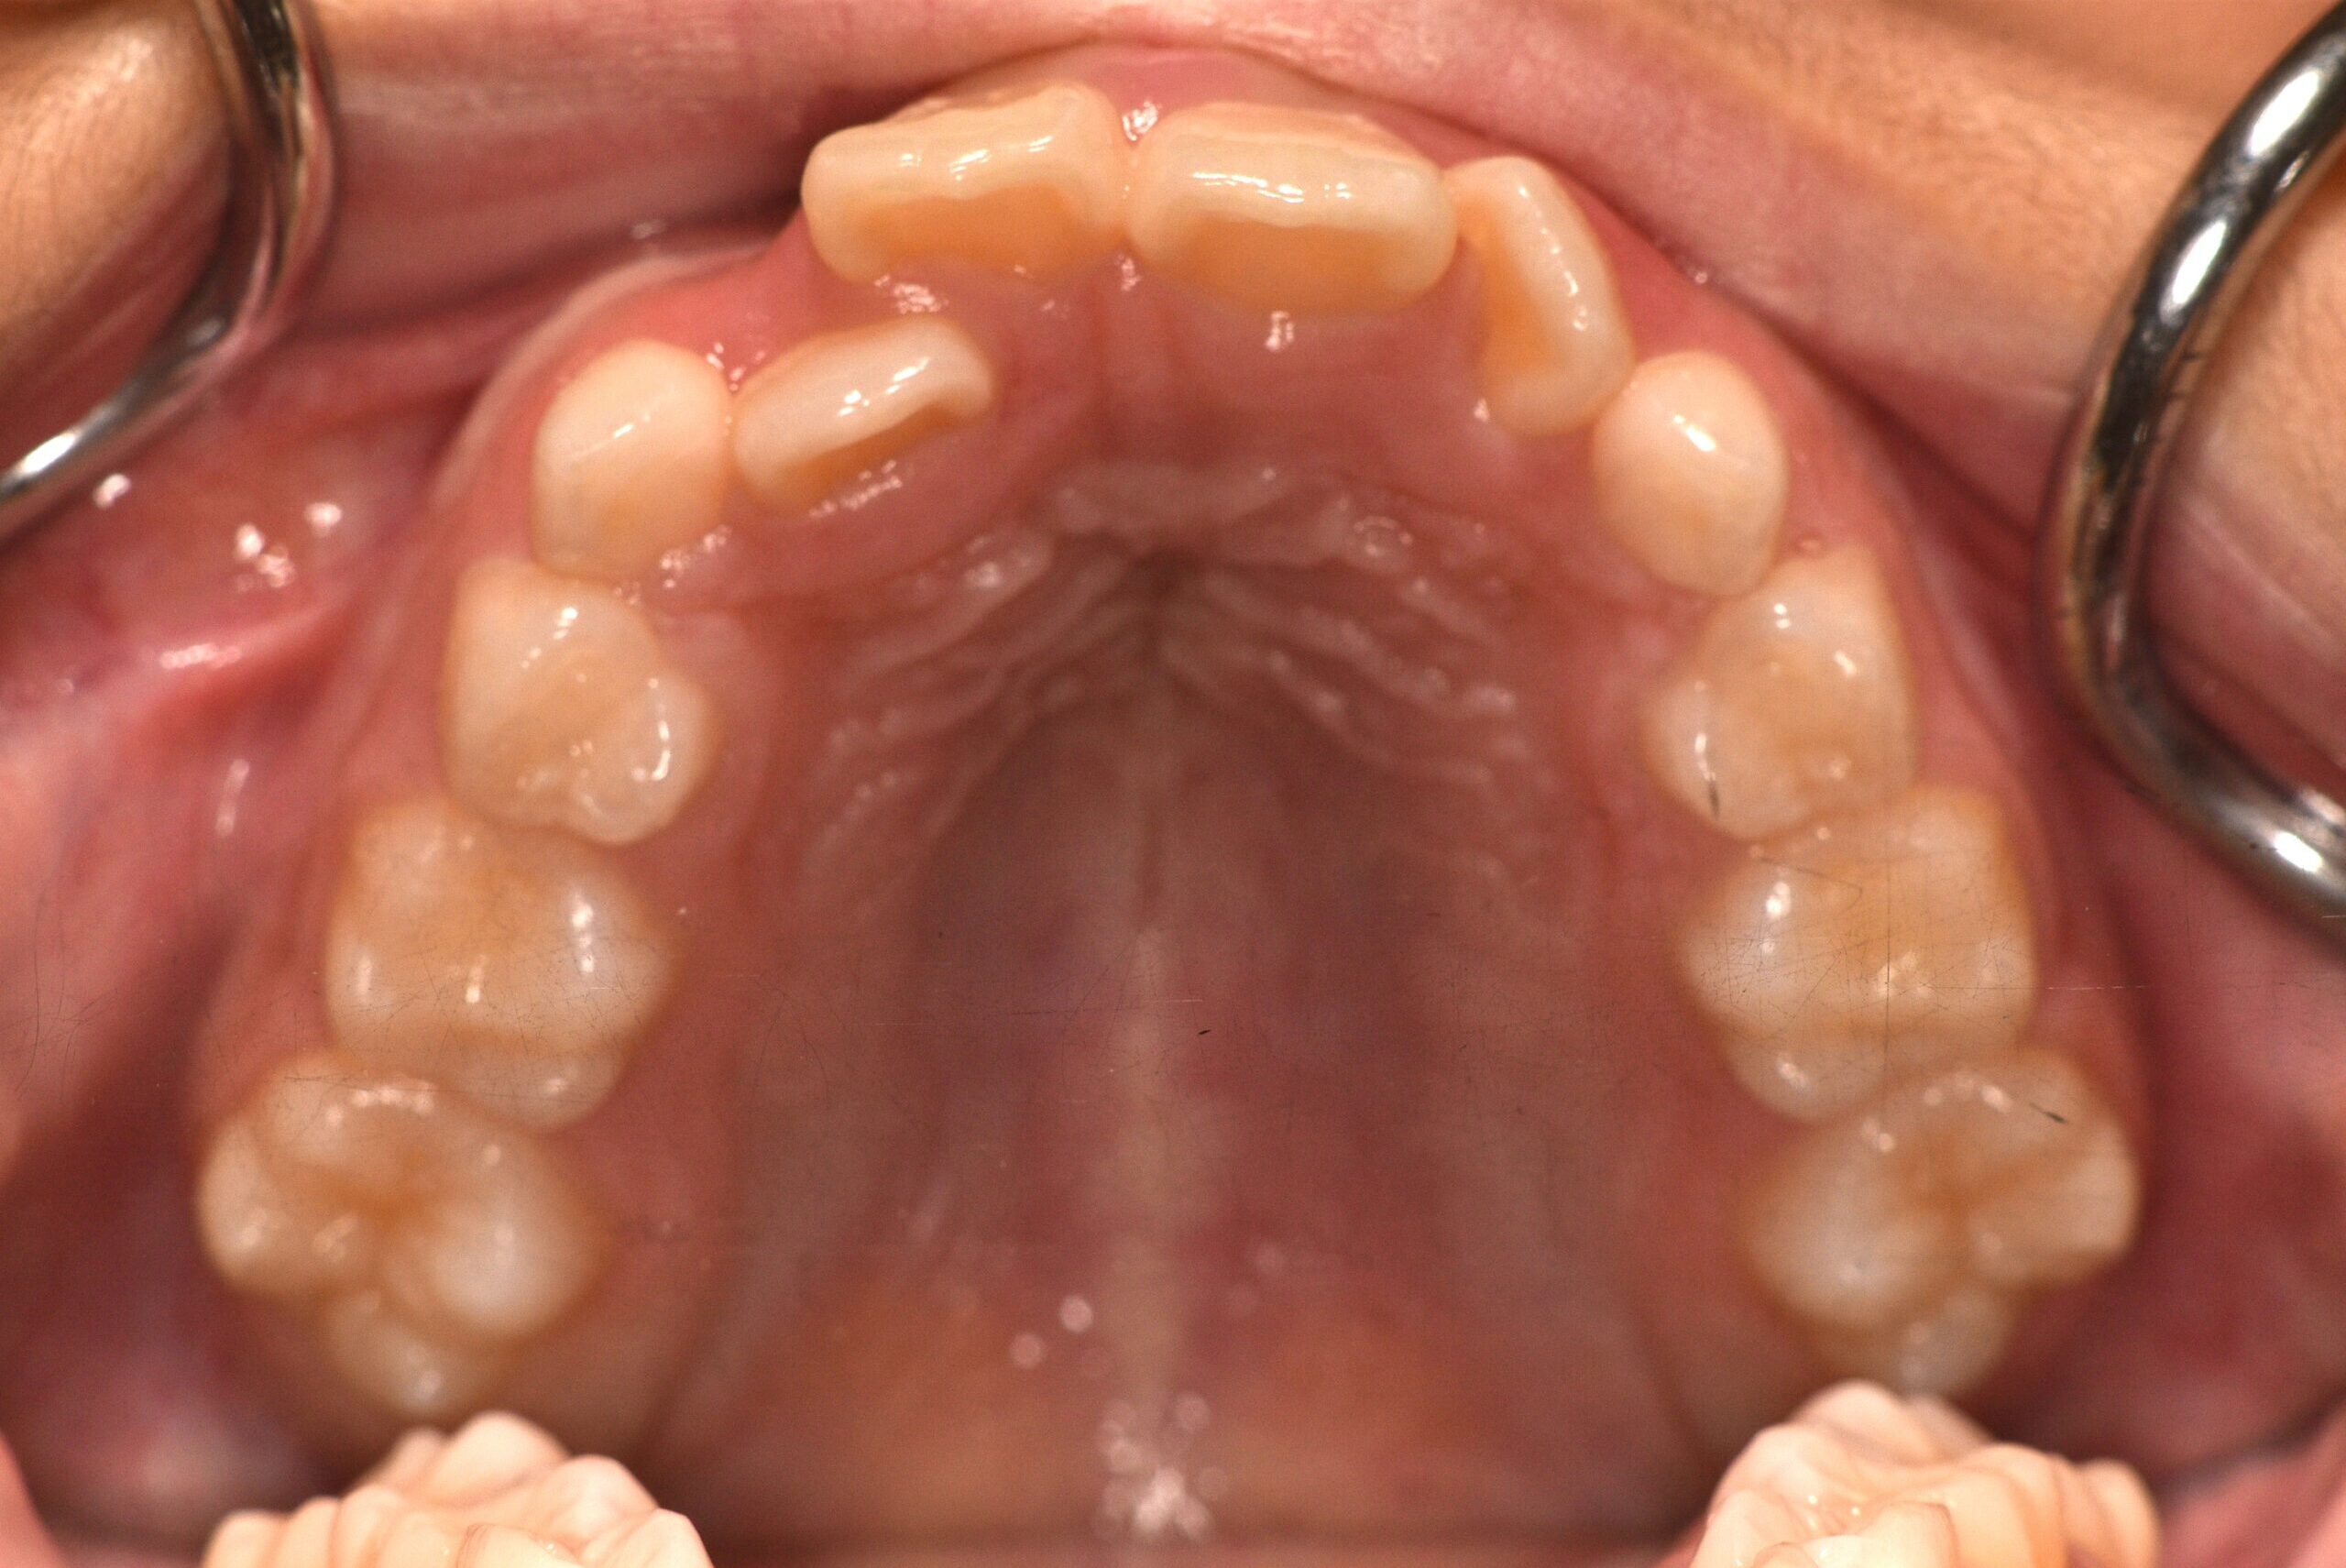

動的治療終了時

症例 症例 症例 症例

治療としてはマウスピース矯正(インビザラインファースト)で配列を行い、上下顎の側方拡大と萌出スペースを確保しました。

治療期間は、7ヶ月でした。

今後、側方歯生え変わりまで経過観察を行います。